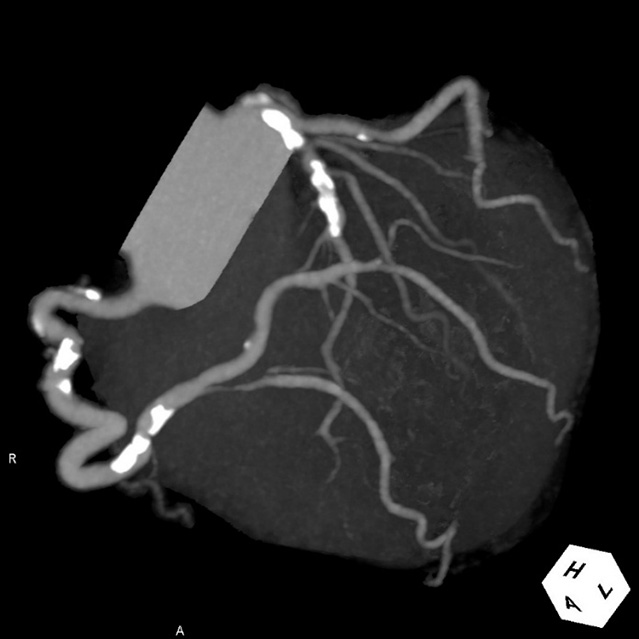

画像診断装置・放射線治療装置紹介

X線CT装置

64列 MDCT Aquilion CX (canon)

|

80列 MDCT Aquilion PRIME (canon)

80列 MDCT Aquilion PRIME SP(canon)

大きなトンネルの中に体を入れて、X線をあてて体の輪切りの写真を撮ります。CT検査には、単純CT検査と、造影剤を注射して撮影する造影CT検査があります。